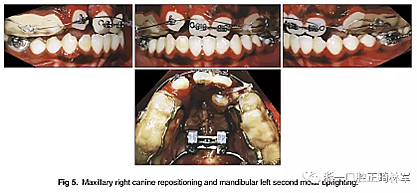

幾個(gè)月后,拔除上頜乳尖牙,應(yīng)用0.018×0.025英寸規(guī)格的亞歷山大固定矯治器; 上頜中切牙的對(duì)齊由0.014英寸的鎳鈦弓絲開始,而上頜左側(cè)尖牙則是腭側(cè)萌出。在下頜弓中,應(yīng)用舌側(cè)弓和第二前磨牙托槽來實(shí)現(xiàn)解除旋轉(zhuǎn)(圖4)。然后,上頜右側(cè)尖牙用0.016英寸的鎳鈦弓絲重新定位,并且使用0.016英寸的不銹鋼片段弓維持中切牙的位置。在下頜弓中,應(yīng)用帶有開放式螺旋彈簧的截面鋼絲直立左側(cè)第二磨牙。它在第一磨牙影響下發(fā)生嚴(yán)重傾斜,受到第三磨牙的壓迫(圖5)。如全景片所示,下頜左側(cè)第二磨牙直立得以實(shí)現(xiàn)(圖6)。1年后,去除上頜擴(kuò)弓器,上下牙弓完全吻合。在上下牙弓中,用0.017×0.025英寸的鎳鈦弓絲進(jìn)行整平。上頜左側(cè)尖牙被移至側(cè)切牙位置; 下頜第一前磨牙被拔除,尖牙開始縮回。